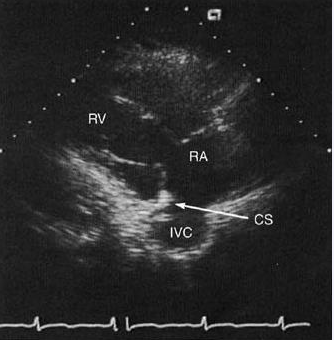

3.右室流入道切面

Schematic and 2D echo images in a right ventricular inflow view

showing the right ventricle (RV) and atrium (RA), tricuspid valve (TV), and ostia of the coronary sinus (CS) and inferior vena cava (IVC).

右室流入道切面